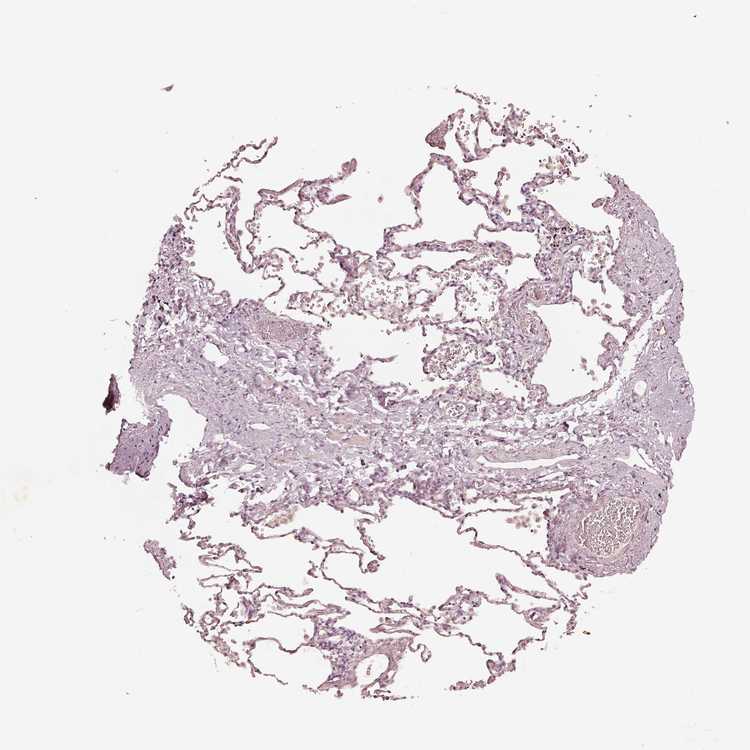

SOFT TISSUE 1 - Antibody stainingi

Antibody staining in the annotated cell types in the current human tissue is reported as not detected, low, medium, or high, based on conventional immunohistochemistry profiling in selected tissues. This score is based on the combination of the staining intensity and fraction of stained cells.

Each image is clickable and will lead to virtual microscopy that enables deeper exploration of all samples and also displays staining intensity scores, fraction scores and subcellular localization as well as patient and tissue information for each sample.

Antibody HPA061969

Fibroblasts Not detected